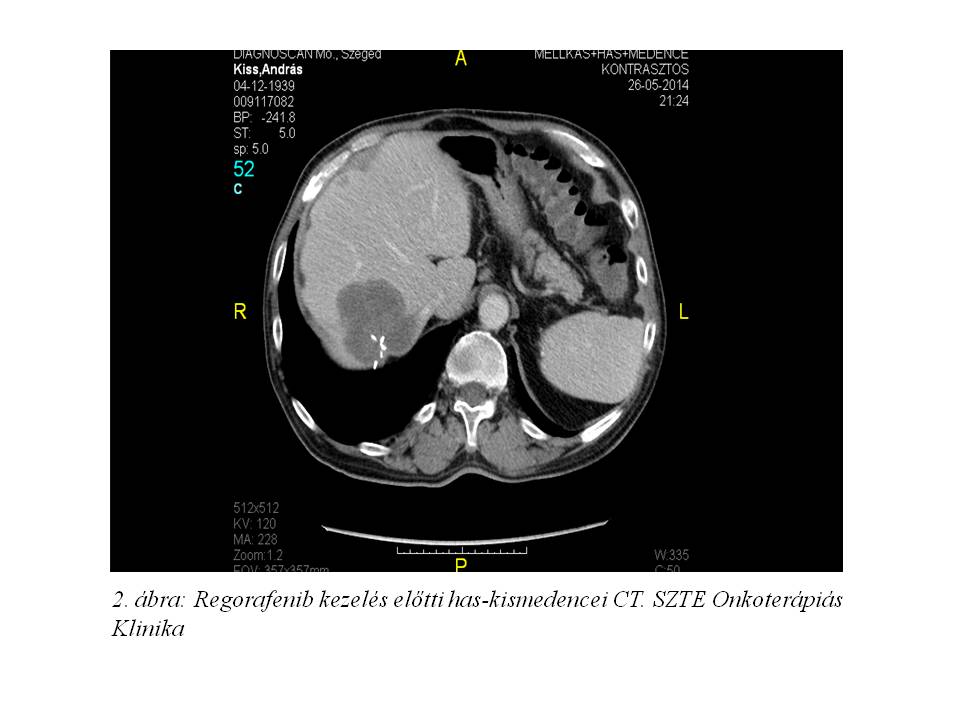

2013 augusztusban a staging vizsgálatok a hepatikus és pulmonális áttétek progresszióját írták le, mely miatt terápiaváltásra kényszerültünk. Kapecitabin monoterápia indult a korábbi 5-FU kezelés mellékhatásaként észlelt hasmenés miatt 25%-os dózisredukcióval, melyet 8 cikluson keresztül kapott a beteg. Ekkor újabb progresszió igazolódott (1. ábra, 2. ábra).

Közben, miután az EMA törzskönyvezte a regorafenibet olyan kolorektális rákban szenvedő betegek kezelésére, akiket korábban már kezeltek a rendelkezésre álló terápiákkal, Egyedi Méltányossági Kérelem került beadásra. Miután az engedélyt megkaptuk, regorafenib kezelés indult 2014 áprilisban utolsó aktív kezelési lehetőségként.